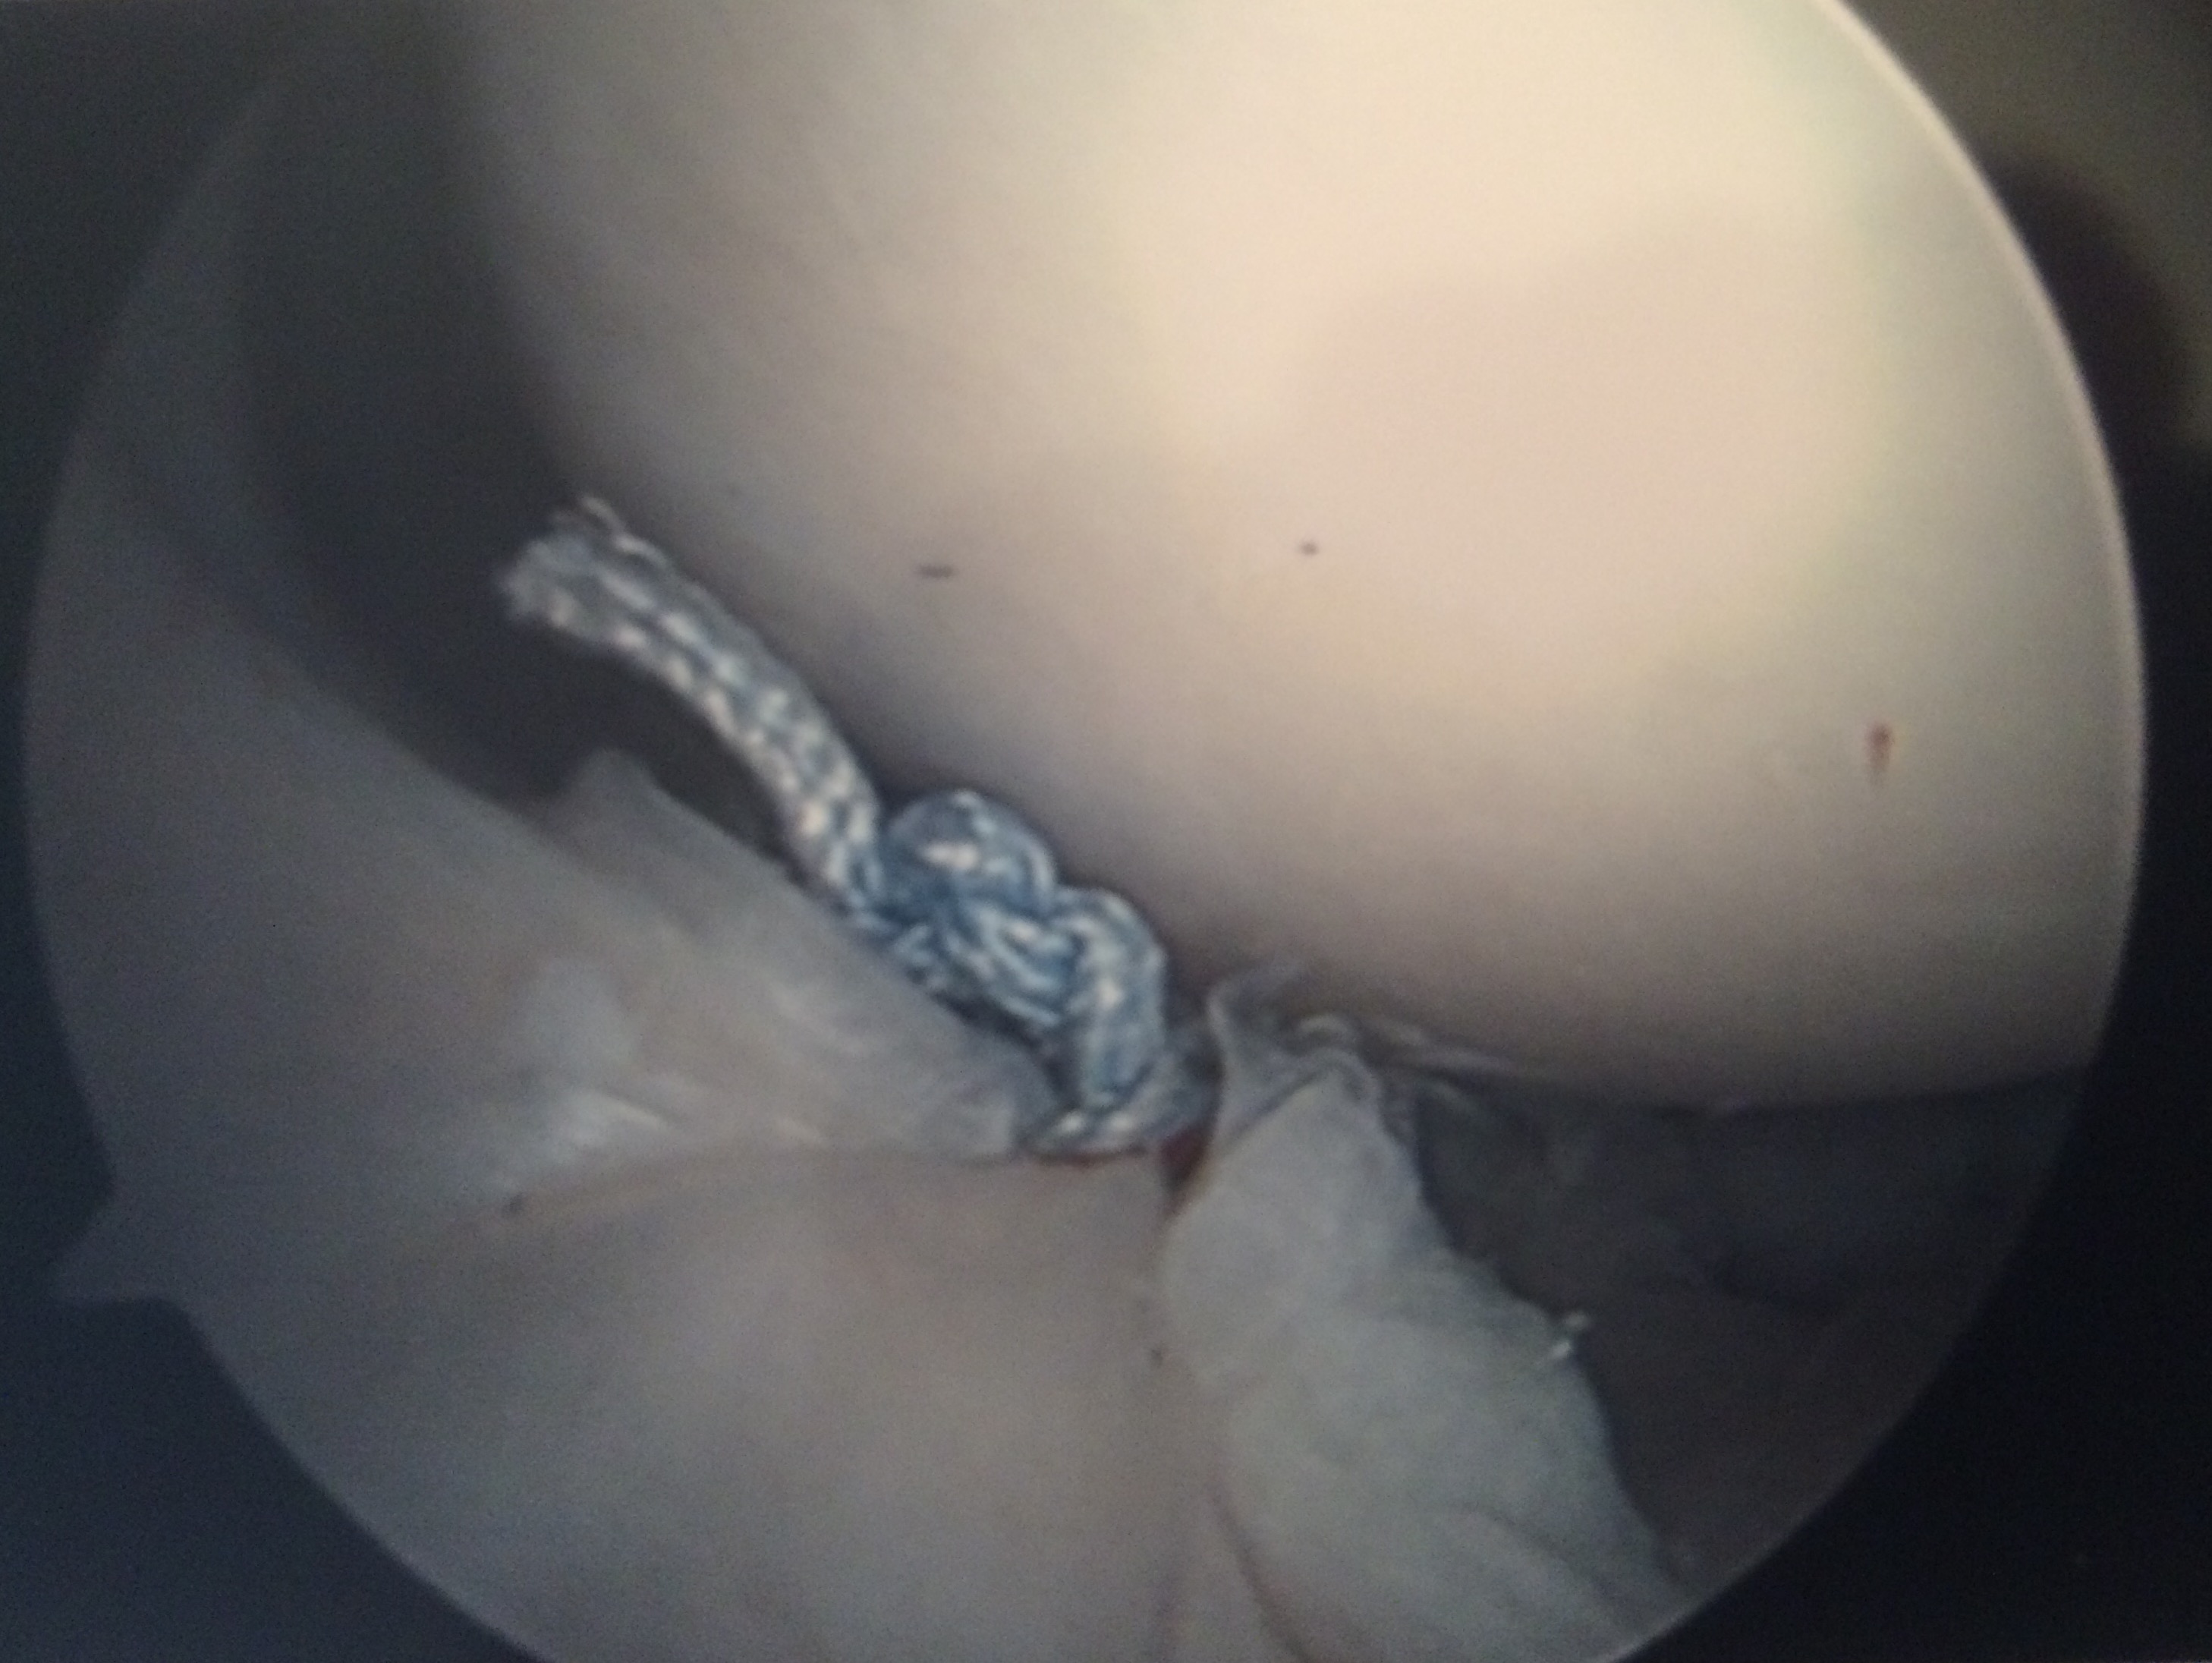

I had shoulder surgery. I love to rock climb, and unfortunately, this led to an injury. I tore my labrum, and had to have an arthroscopic repair surgery. I was in a sling for a month, and for twelve weeks, couldn't lift anything, run, bike, ride my motorcycle, or do a lot of other things. I still haven't been able to climb yet, though I'm going to be very slowly starting back up in January, starting with beginner bouldering. This injury actually kicked off some depression that I've been dealing with ever since. Meds, friends, and therapy are helping, in addition to slowly getting to go back to doing what I love. Before my injury I was climbing better than ever before - crushing a 5.11 outside, and working on 5.11+ and 5.12 inside. In the time since the surgery, I've picked up table tennis and read quite a bit.